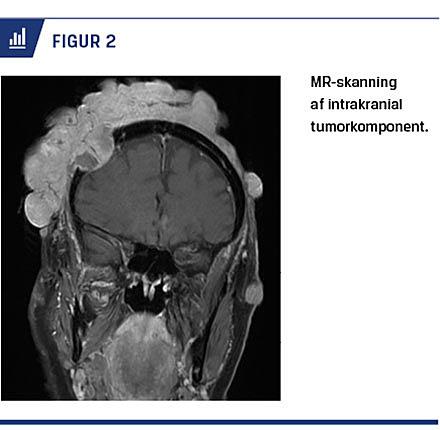

En 76-årig kvinde blev henvist til en plastikkirurgisk afdeling til excision af en turbantumor. Der var tidligere excideret cylindromer, senest et på højre side af hovedet med manglende heling. En MR-skanning viste en 3,5 × 2,6 cm defekt i højre parietalregion med underliggende intrakranial tumorkomponent (Figur 2). Klinisk var skalpområdet præget af tætsiddende små, hårde, glatte lyserøde tumorer (Figur 1A).